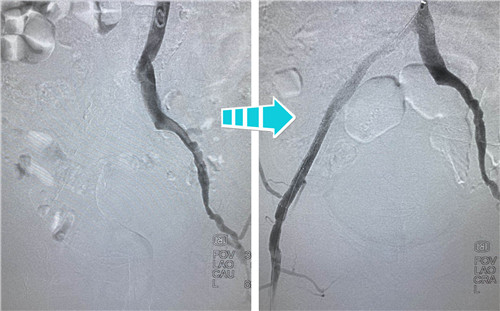

身經(jīng)百戰(zhàn)的放射科介入團(tuán)隊(duì),在南京鼓樓醫(yī)院血管外科王煒教授的指導(dǎo)下,決定為吳老先生行兩側(cè)髂血管成形術(shù)。手術(shù)當(dāng)天,選擇經(jīng)左側(cè)肱動(dòng)脈入路,置入90CM長(zhǎng)鞘,在導(dǎo)絲指引下,小心翼翼地通過左側(cè)股總動(dòng)脈狹窄段,給予球囊擴(kuò)張,精確定位并植入支架,左側(cè)髂血管就此打通??紤]后期患者情況改善,可能還需要處理股淺動(dòng)脈,專家們還預(yù)保留了股淺和股深開口。